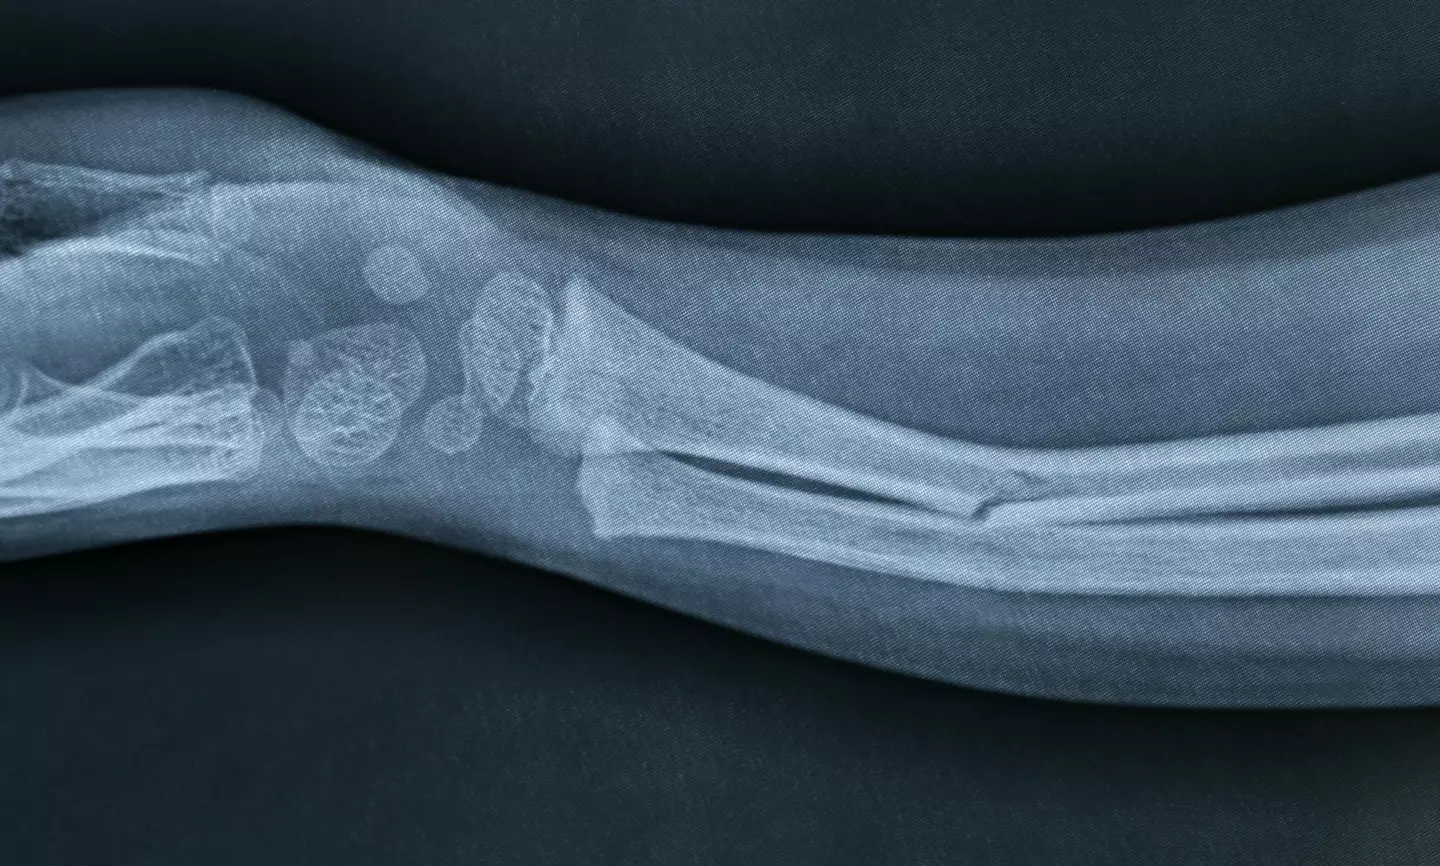

Broken bones,